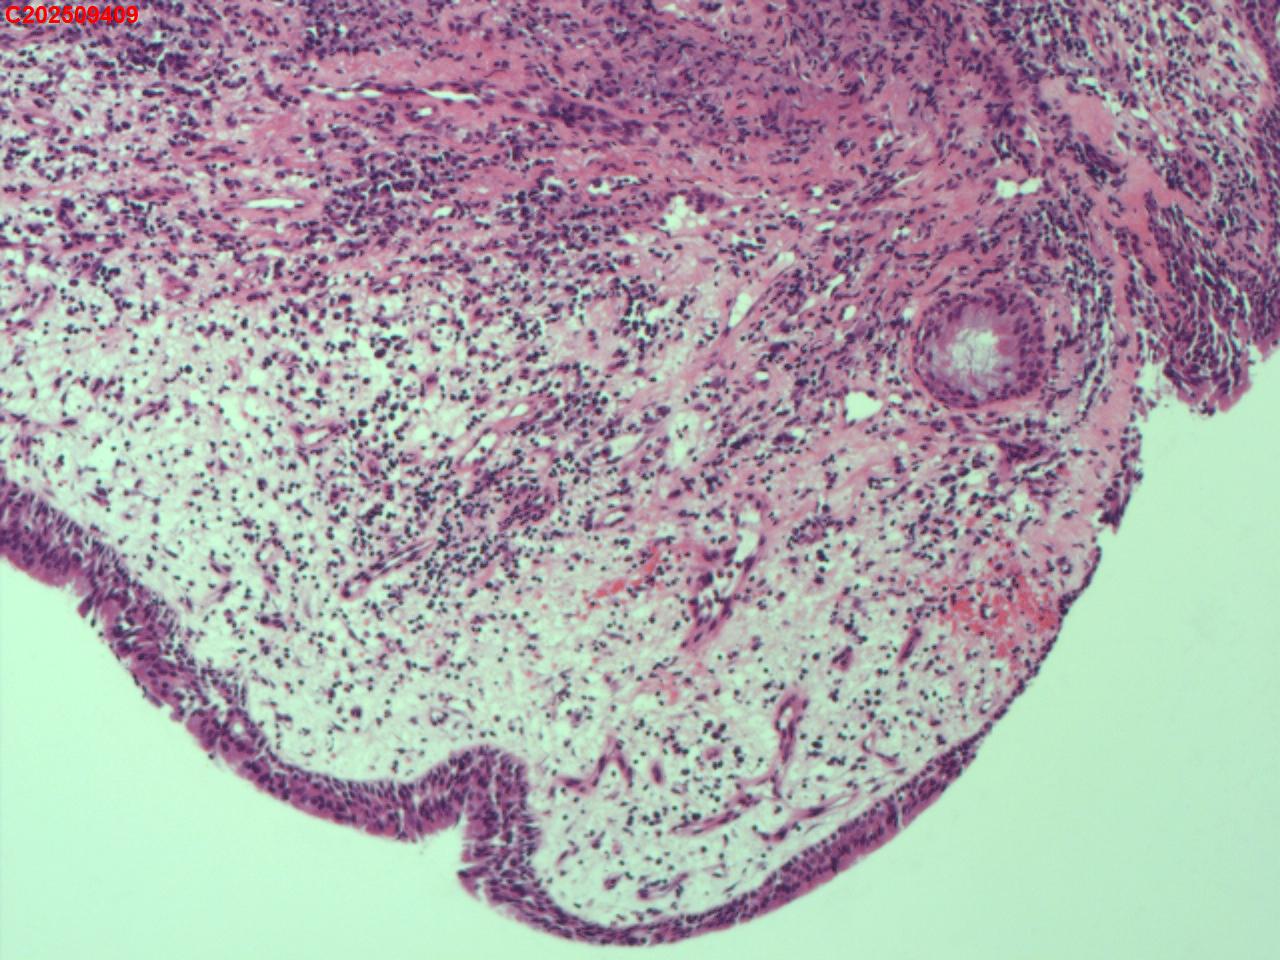

性别年龄62岁临床诊断社区获得性肺炎,肺占位性病变带除外

一般病史胸部CT:双肺可见多发斑片状、结节状高密度影,右肺上叶及左肺下叶病灶内见多发空洞,右侧少量胸腔积液。

标本名称纤支镜咬检

大体所见纤支镜:气管通畅,隆突锐利。右肺主支气管通畅,右肺上叶见少量痰液,负压吸引后见上叶开口干酪坏死物质附着,上叶各段级支气管通畅未见新生物及坏死物质,中叶、下叶背段支气管通畅,下叶基底段见新生物阻塞气道,粘膜无充血。左肺主支气管、上叶、下叶及各段级支气管通畅,粘膜无充血,未见新生物及坏死物。

考虑:支气管炎性息肉